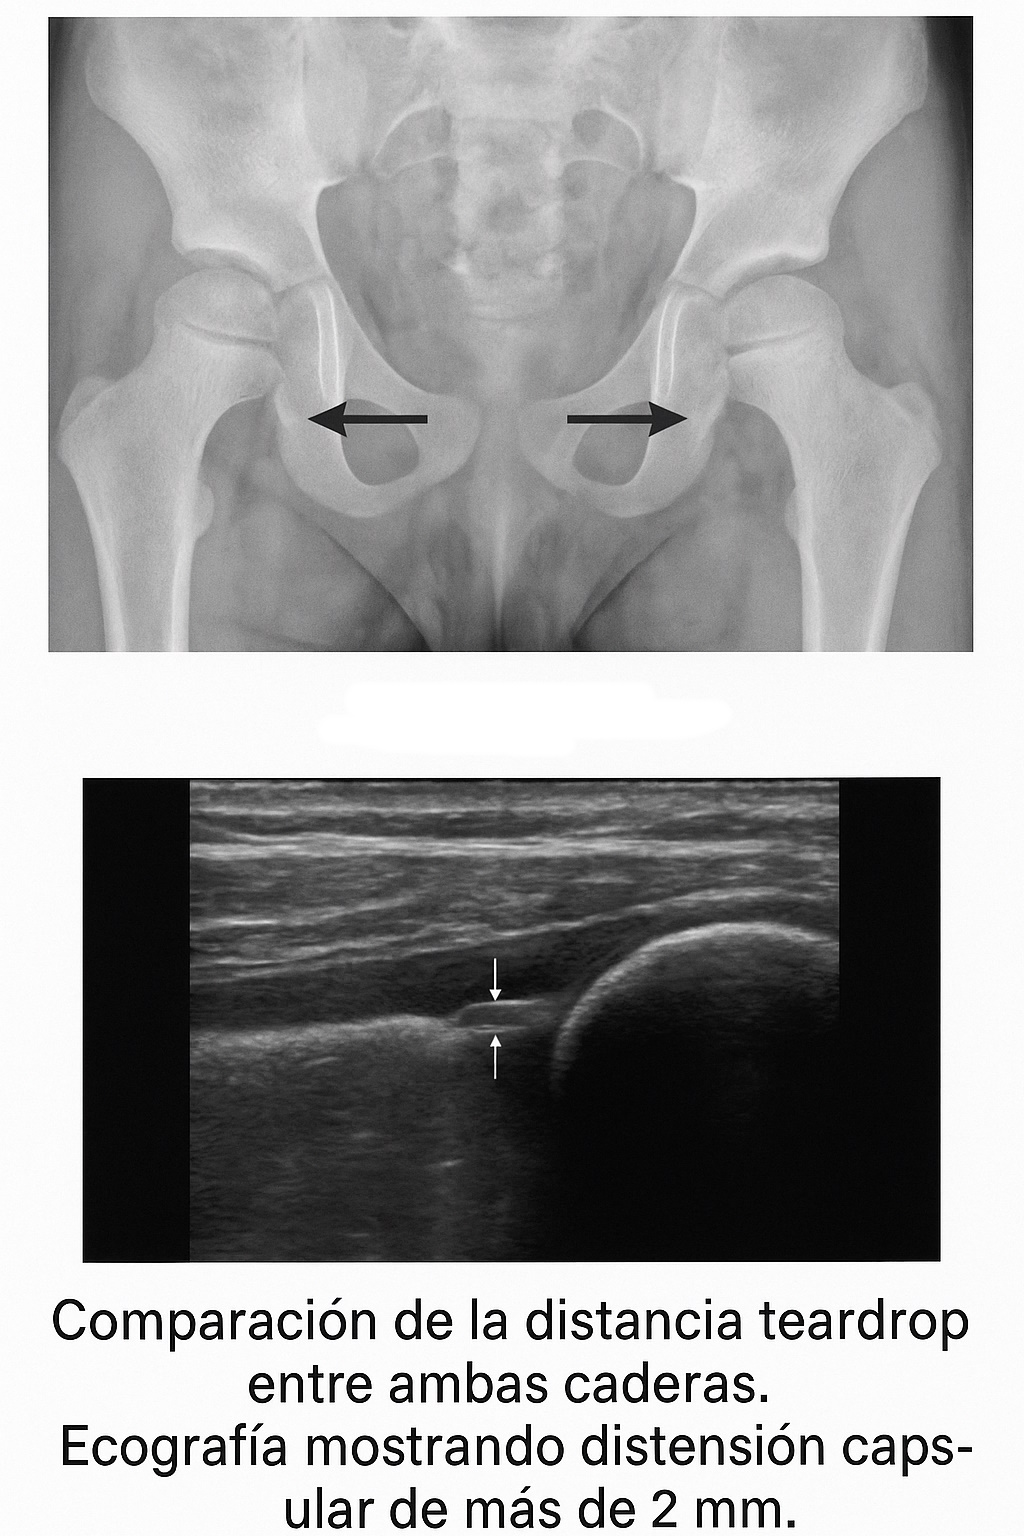

- El espacio articular puede estar levemente aumentado en la cadera afectada (imagen 1).

- Si hay aumento del líquido sinovial o el paciente está en una fase precoz de la enfermedad de Legg-Calvé-Perthes, las radiografías pueden mostrar un aumento de la distancia del teardrop (definida como la distancia desde el margen lateral de la lágrima pélvica hasta la parte medial de la cabeza femoral en una proyección anteroposterior de pelvis, figura 1). Esta distancia, comparada con el lado sano, debe ser igual o menor a 1 mm (imagen 2).

- Atención: algunos autores llaman a este hallazgo signo de Waldenström, que corresponde al aumento de la distancia entre la cabeza femoral y la cavidad cotiloidea, medida a la altura de la imagen en lágrima. Debe compararse con la cadera contralateral, que debe ser normal.

- En un estudio, el 58% de los pacientes con sinovitis transitoria tenían signo de Waldenström positivo (desplazamiento superolateral de la cabeza femoral). Un derrame articular importante puede ocasionar este desplazamiento y el ensanchamiento del espacio intraarticular medial (imagen 1).

Imagen 1: Leve aumento del espacio articular en la cadera afectada. El espacio es más ancho en el lado izquierdo. Diferencias superiores a 1 mm indican líquido articular. También puede observarse desplazamiento superolateral de la cabeza femoral (signo de Waldenström).

Figura 1: Diagrama de la articulación coxofemoral como se puede ver en la radiografía frontal de pelvis. Obsérvese la configuración de lágrima anteroinferior del acetábulo, la fovea central, y la distancia de la lágrima (flechas). El límite lateral es la parte más medial de la cabeza femoral. El límite medial es el margen lateral de lágrima.

Imagen 2: Comparación de la distancia teardrop entre ambas caderas.